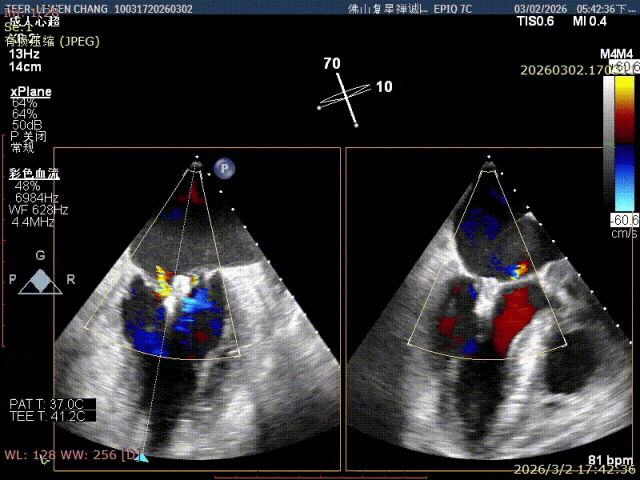

彭宇程教授团队行房间隔穿刺,高度4.3cm,依次置入导引鞘和XW0612瓣膜夹,瓣上精准调整测试瓣膜夹Position、Orientation、Trajectory,跨瓣后打开瓣膜夹捕捞,确认前后瓣叶平铺在夹臂上,Gripper down后,慢慢关闭瓣膜夹夹臂,释放前后都进行评估,确认夹子内外两侧仍存在少量反流,决定在第一枚夹子外侧补放一枚SN0409瓣膜夹,瓣膜夹捕获瓣叶后,评估剩余瓣口面积,跨瓣压差,残余反流,取得优秀的效果,决定释放;术后即刻评估显示二尖瓣反流得到显著控制,跨瓣压差约5mmHg,肺静脉逆流征象明显改善,血流动力学效果优异。

释放XW0612瓣膜夹

组织桥稳定

夹子内外侧均有微量反流, 且一区还存在脱垂

在夹子外侧补放一枚SN0409夹

外侧反流消失

反流减少至微量